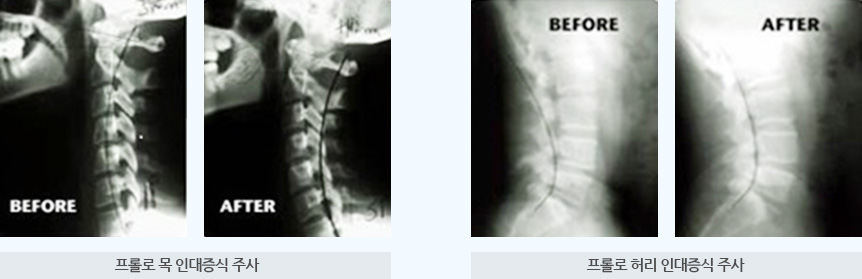

PROLO 테라피 치료방법

뼈와 관절 주위조직에 12.5%~25%의 혼합 텍스트로를 주입해 손상된 조직의 재생을 촉진하고 관절과 주변조직의 강화를 통해 통증을 개선하는 치료입니다.